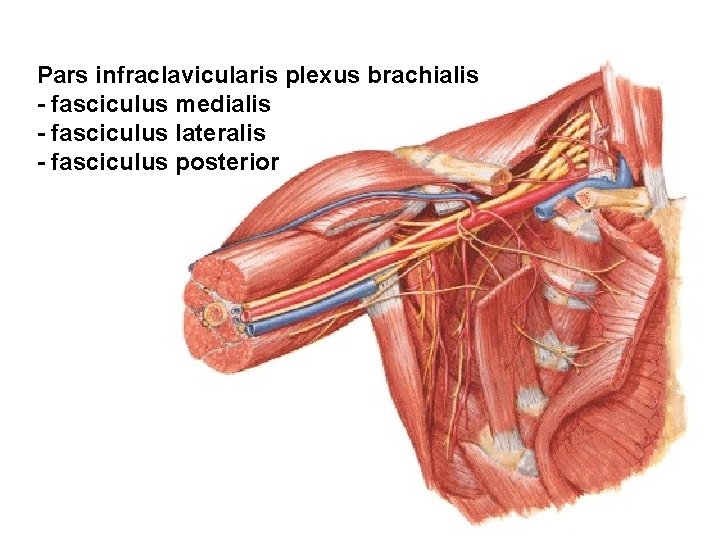

Pars infraclavicularis plexus brachialis - fasciculus medialis - fasciculus lateralis - fasciculus posterior

PARS INFRACLAVICULARIS (terminal branches) Fasciculus posterior - n. axillaris - n. radialis Fasciculus lateralis - n. musculocutaneus - radix lateralis n. mediani Fasciculus medialis - radix medialis n. mediani - n. ulnaris - n. cutaneus antebrachii med. - n. cutaneus brachii medialis